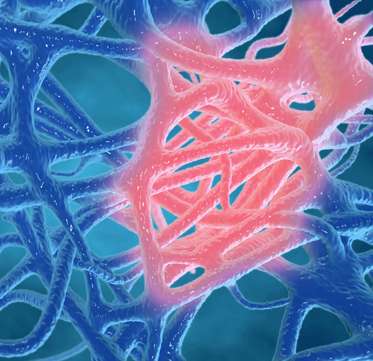

Its effectiveness is built on a unique multi-target method known as the I-M-F Protocol, addressing Inflammation, Muscle tension, and Fibrosis to target the root cause of pain rather than simply masking symptoms.

- The I-M-F process stands for Inflammation, Muscle tension, and Fibrosis, representing a harmful chain reaction within the body.

- It begins when chronic inflammation activates immune responses, releasing enzymes and cytokines that irritate tissues.

- This irritation triggers muscle tension, causing stiffness, pain, and restricted movement. Over time, continuous inflammation and tension lead to fibrosis, the buildup of scar tissue that further limits flexibility and joint mobility.

- In simple terms, the I-M-F process is the root cause of persistent joint and muscle pain, as it turns temporary inflammation into long-term physical damage and discomfort